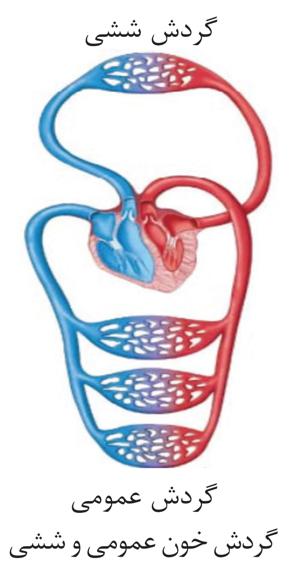

کمبود آب، اکسیژن و مواد مغذی یا انباشته شدن مواد دفعی یاختهها مثل کربن دیاکسید و مواد دفعی نیتروژن دار از جمله مواردیاند که ادامۀ حیات را تهدید میکنند. حفظ وضعیت درونی بدن در محدودهای ثابت(همایستایی)، برای تداوم حیات، ضرورت دارد.

مواد دفعی بدن ما از طریق ساختارهایی مثل کلیه، شش، پوست و لولهی گوارش دفع میشود.